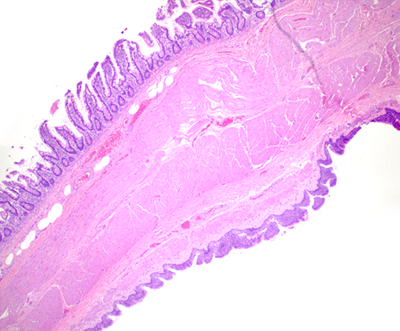

Figure 1. Histology demonstrates the cyst (bottom) directly attached to the intestinal wall (4x).